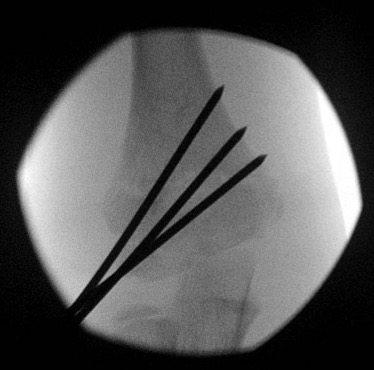

2 x lateral K wires

Advantage

- no risk to ulna nerve

Disadvantage

- if not correctly done, can be unstable

Technique

- hold elbow in flexion

- place K wire into lateral condyle

- place other index finger on the humerus to guide aim

- 2 x lateral 1.6 mm K wires (consider 2 mm K wires in larger children)

- one K wire on the direct lateral surface, just lateral to the capitellum

- one on the capitellar surface

Points

- must engage medial and lateral columns (bicortical)

- make pins divergent for increased stability

- only need 3rd pin if first two not divergent enough

Check stability

- place elbow into extension